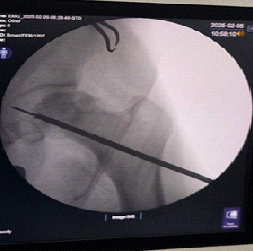

Subsequent attempts to free the broken tip using a thicker guidewire inadvertently pushed it further toward the joint cavity. Eventually, it was visualized to be lodged in the acetabulum on fluoroscopy. To retrieve the broken wire, the remaining part of the guidewire was aligned with the broken tip (Fig. 2) over which a dynamic hip screw inner reamer was gently hand-reamed (Fig. 3). This made sure the reaming did not create another tract. This maneuver facilitated mobilization of the wire but also pushed it further (Fig. 4). Finally, using an arthroscopic grasper under continuous fluoroscopic guidance, the fragment was successfully retrieved (Fig. 5).

Figure 3: Guide wire pushed further inside the acetabulum cavity while trying to over-ream.

Figure 4: Broken tip migrating into the acetabulum.